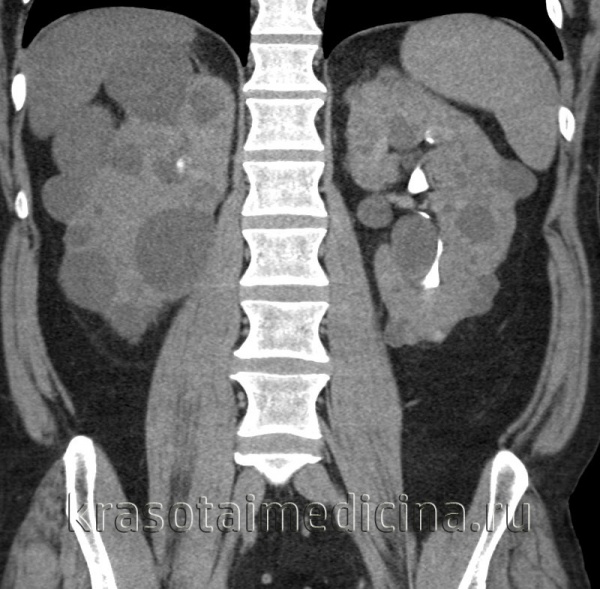

Рисунок 5,6, КТ-изображение в корональной проекции, поликистоз почек, кисты печени, поджелудочной железы.

• Множественные билатеральные кисты в увеличенных почках:

о Осложненные кисты:

- Геморрагические кисты: гиперденсное содержимое (60-90 HU), возможны пристеночные кальцификаты

(Слева) КТ без контрастирования, аксиальная проекция: поликистозное поражение почек и печени. В то время как большинство кист почки гиподенсные, периферические кисты левой почки - гиперденсные, сравнимые по плотности с геморрагическими кистами.